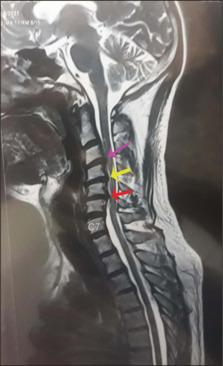

Among 182 examined cervical vertebrae, unilateral complete accessory foramen transversarium was found in 23 vertebrae (12.63%), bilateral complete in 19 (10.44%), bilateral incomplete in 6 (3.29%), unilateral complete double in 4 (2.19%), and unilateral complete absence of foramen transversarium in 3 (1.64%). Stenosis due to aberrant osteophytes was noted in 9 vertebrae (4.9%). Out of 190 patients, three males presented with cervical kyphosis, severe spinal canal stenosis, and spinal cord compression due to ossification of the posterior longitudinal ligament and osteophyte complexes at C3-C6, with the most significant compression at C5-C6.

在182个检查的颈椎中,发现23个椎体(12.63%)有单侧完全性副横突孔,19个椎体(10.44%)有双侧完全性副横突孔,6个椎体(3.29%)有双侧不完全性副横突孔,4个椎体(2.19%)有单侧完全性双横突孔,3个椎体(1.64%)有单侧完全性横突孔缺如。9个椎体(4.9%)因异常骨赘导致狭窄。在190名患者中,三名男性因C3 - C6后纵韧带和骨赘复合体骨化出现颈椎后凸、严重椎管狭窄和脊髓受压,C5 - C6处受压最为明显。